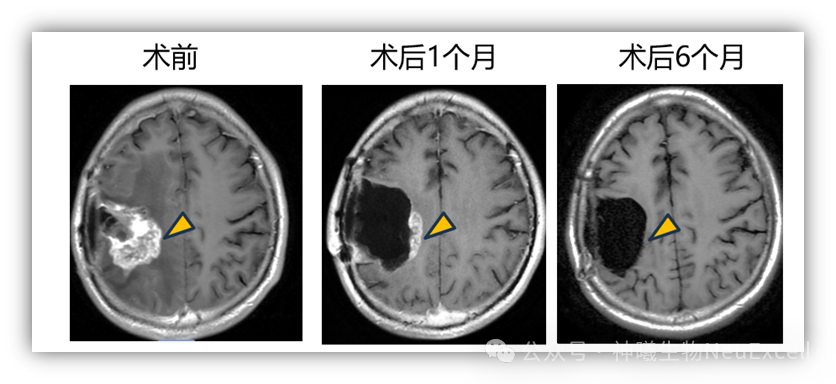

肿瘤切除+瘤腔内注射的1例患者,术后观察到肿瘤逐渐缩小并完全消退,达到影像学CR(complete response)(图2)。